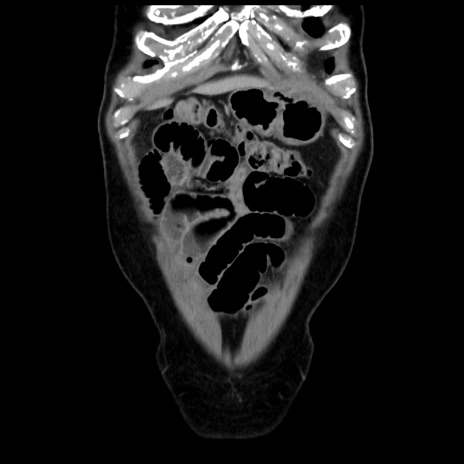

横断像